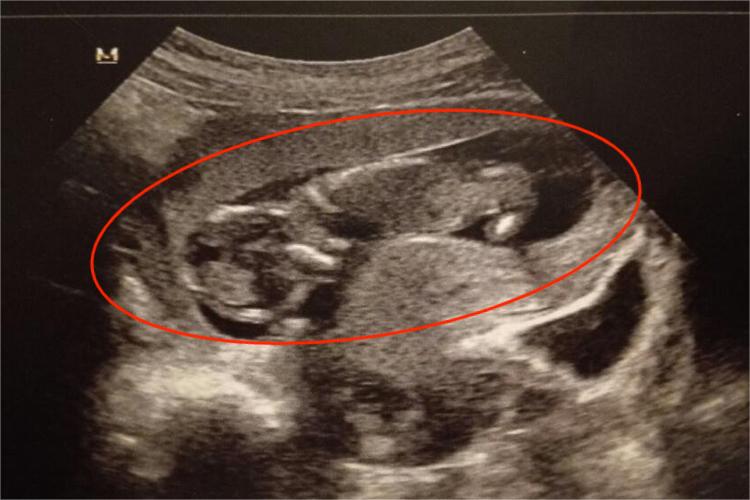

胎势是指胎儿在子宫内的姿势,在正常羊水量时,胎儿头略前屈,背略向前弯,下颌抵胸骨,上下肢屈曲于胸腹前,脐带位于四肢之间。若胎儿的胎龄较小,可在羊水中自由活动,在子宫内可为蜷缩样,但面部及前胸朝向下方,表现为胎儿在子宫趴着,属于正常的胎势。

胎儿在子宫趴着一般无需特殊处理,怀孕7个月左右一般会定胎位,需要定期去正规医院做产检,查看胎儿发育情况以及羊水量多少,若长时间羊水量比较少,可能会引起胎儿出现缺氧。